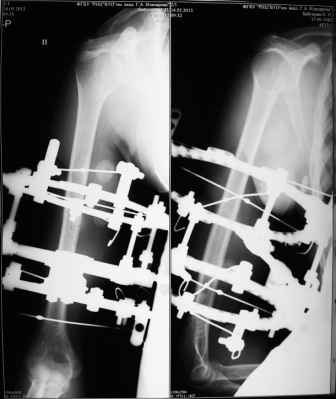

Внеочаговый остеосинтез по методике Илизарова - ЧКДО

Вот типичный пример консолидации с минимальной периостальной реакцией.

Фото в аппарате. За редким исключением диафизарные переломы плеча фиксирую двумя опорами. Предельно функционально. Пациенты на второй неделе по моей рекомендации широко пользуются конечностью в быту - убираются, готовят, моют посуду...

Фото через 3 месяца после снятия аппарата